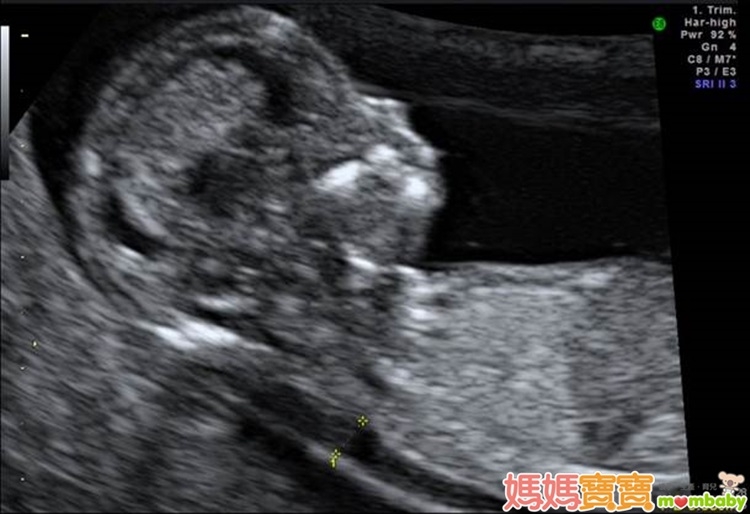

利用高解析度的超音波來檢查胎兒頸部透明帶厚度,以確認胎兒是否具備染色體或構造異常等疑慮,進而接受更進一步的評估,正是這個產檢項目的宗旨。頸部透明帶的測量部位,為胎兒頸椎表皮與表皮底下軟組織的間隙,之所以會發展這樣的篩檢方式,是因為藉由以往的臨床經驗中逐漸得知,染色體與器官構造異常的胎兒,頸部透明帶似乎皆有變厚的傾向,例如唐氏症、透纳氏症候群、先天性心臟病等,這些疾病往往合併胎兒膠原組織組成改變,或淋巴及心血管循環出現異常,進而導致頸部透明帶變得較厚;因此,醫界便開始利用這個現象來回推檢測,觀察頸部透明帶較厚的胎兒是否有較高機率發生異狀,才會演變為現今的胎兒頸部透明帶篩檢。

頸部透明帶的檢查週數為懷孕第11週~第13週又6天之間,有些準媽媽可能會以月經週期來推算懷孕週數,但如果忘了最後一次的月經日期或平常月經不規則的孕婦,醫師會利用超音波來測量胎兒的頭臀徑(頭到臀部的長度,也就是胎兒坐姿高度),若頭臀徑介於36~84公厘之間,也達到適合檢查頸部透明帶的標準。